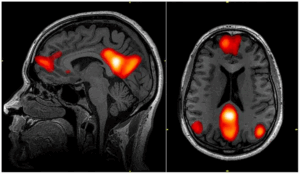

Melatonin is a hormone that regulates this sleep-wake cycle. Light exposure during the day suppresses melatonin levels, while darkness at night increases them and therefore induces sleep (4). This effect correlates with the fact that throughout much of history, humans’ sleep-wake schedules were aligned with sunrise and sunset (5). Light detection by intrinsically photosensitive retinal ganglion cells (ipRGCs), located in the retina (6), influences melatonin levels (2). ipRGCs are extremely sensitive to blue wavelengths; therefore, the detection of these wavelengths greatly suppresses melatonin levels.